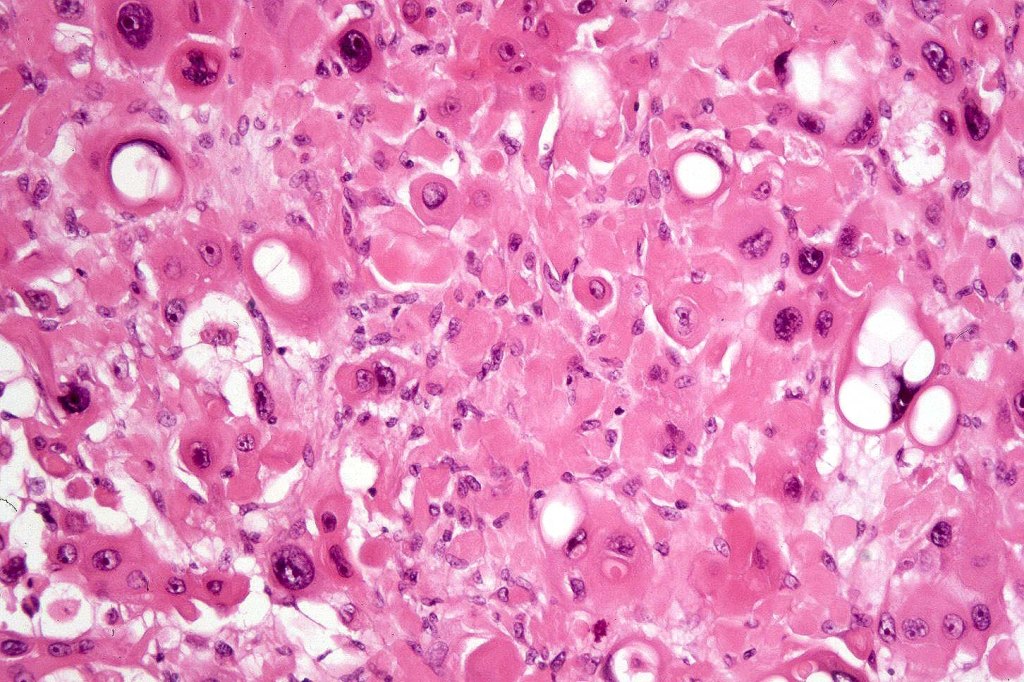

•Acantholysis gives rise to a pseudoglandular appearance

•Variable pleomorphism & mitotic activity

•Exceptional associated signet-ring cell change (signet ring cell squamous carcinoma)

•Absence of epithelial mucin